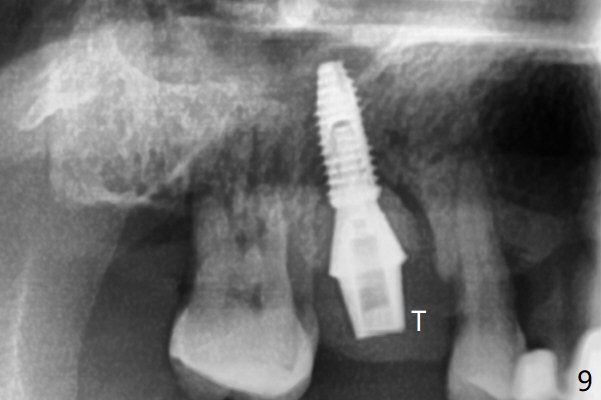

53岁男吸烟,牙周炎,咬合力大,3号牙颊侧(图一),腭侧(图二:P)牙龈退缩,尤其是近中颊侧根(图一:MB),拔牙后,中隔冠方(表面)有好像健康的牙龈(图三:*),近中,远中连接处切开(图三:虚线),将中隔牙龈推向近中颊侧牙槽窝(图四:箭头),修复退缩牙龈,而且暴露下面中隔(S),接着在它上面导板钻洞,避免软组织创伤。利用报废植体试图内提升(图五(红虚线:窦底)),最终正式植体完成提升(图六:黑*),初步在牙槽窝深部放置粘性骨粉(白*)后,放入基台,之后再次在植体,基台周围放置骨粉(图七:*),最后借助临时牙冠(图八,九:T)和外衬里(图八:R)封闭牙槽窝开口,G是近中颊侧迁移的牙龈。植体垂直进入上颌窦可以减少窦膜破裂(图五,六,九),术后没有鼻出血。术后1个月临时牙冠松动,去除牙冠和基台,安置愈合帽(图十)。表面骨粉遗失,但是颊侧移位的中隔牙龈好像帮助软组织预后。